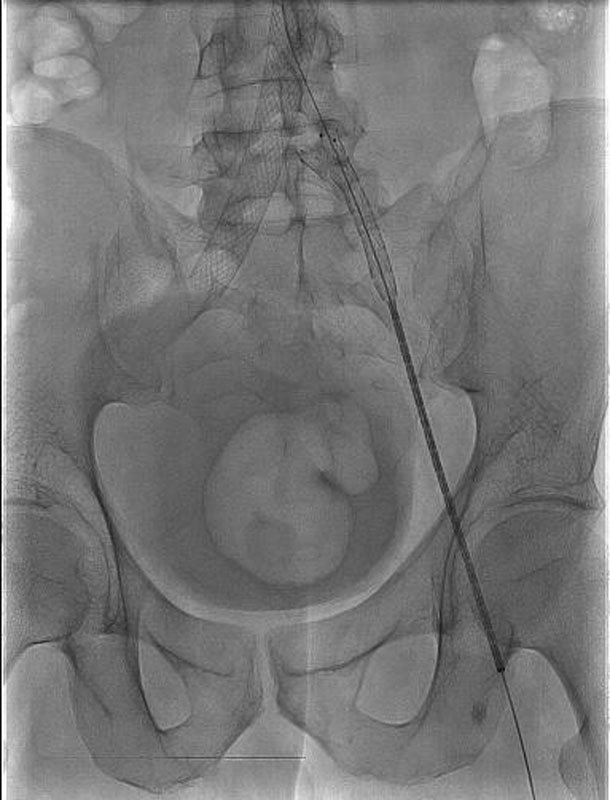

Впервые в России имплантирован венозный стент нового поколения VENOVO, выполнена реканализация и стентирование глубоких подвздошных вен у пациента с синдромом нижней полой вены, развившегося после билатерального илио-феморального тромбоза